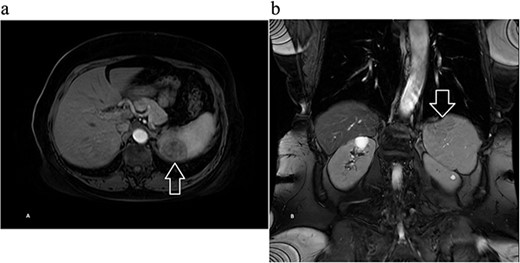

Next, magnetic resonance imaging (MRI) of the abdomen with IV contrast was obtained and revealed a well-circumscribed 3.7 × 3.7 cm solid lesion in the lower pole of the spleen with a decreased signal on T2, suggestive of atypical hemangioma versus malignancy (Fig. 2). After further discussion with the patient, she opted to undergo robotic-assisted diagnostic splenectomy. She received splenectomy vaccines 2 weeks preoperatively. The operation went smoothly, four robotic ports were utilized, and the specimen was delivered through a Pfannenstiel incision. Postoperatively, the patient’s course was complicated by rectus sheath hematoma and hemoglobin dropped to 6.7 g/dl, and she received one unit of blood with appropriate response. She was discharged home on postoperative day 3, and was doing well during her postoperative checkups.

Magnetic resonance imaging of the abdomen with contrast showing a well-circumscribed 3.7 × 3.7 cm solid lesion in the lower pole of the spleen with a decreased signal on T2 on (a) axial and (b) coronal views with arrow marking the mass.